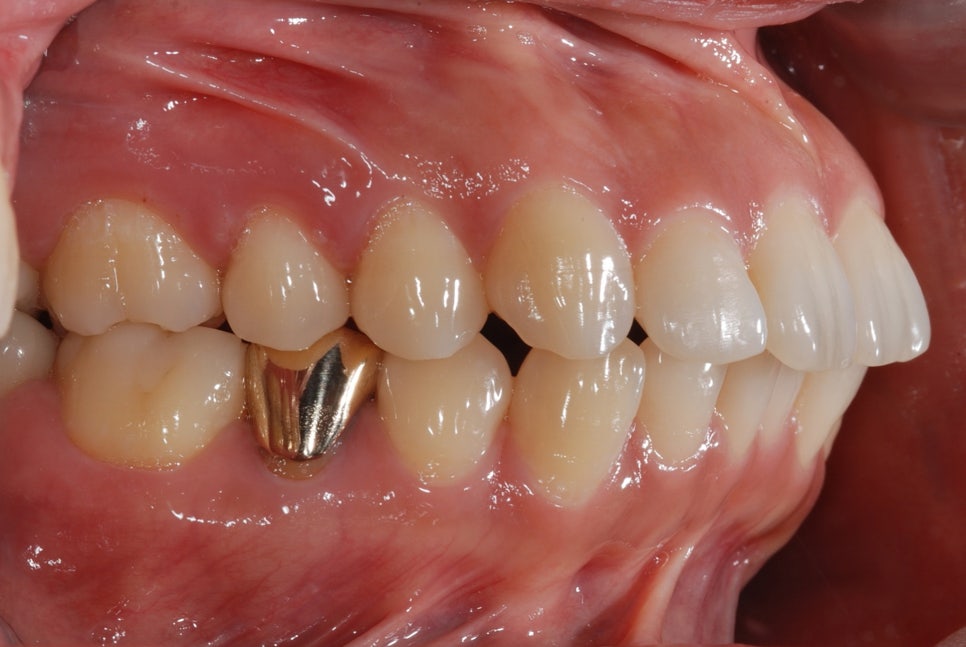

In this patient’s case, the biggest concern was an underbite with the lower jaw developed forward.

As a result of the diagnosis, the teeth were unevenly positioned due to insufficient space,

and because of mandibular overgrowth, the lower front teeth protruded beyond the upper front teeth.

After a detailed analysis of the patient’s facial features, X-rays, and dental arches,

we expanded the shape of the upper and lower arches,

and performed tooth extraction for backward movement of the lower jaw, moving the lower front teeth backward.

In this process, we also precisely adjusted the occlusion so that the temporomandibular joint would not be strained.

Around 12 months later, the extraction spaces had closed, and you can see that the teeth were moving inward well.

The treatment period was about 1 year and 6 months,